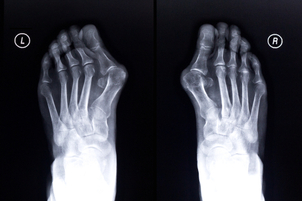

Boční odchylka palce je zřejmá, když pacient stojí bosý. Úhel větší než 15° již neodpovídá normě. Hallux valgus způsobuje bolest a puchýře, výčnělek je citlivý na tlak a tak je velmi bolestivé nosit boty. Valgusová odchylka palce navíc často vede k nedostatku místa pro ostatní prsty.

Před zákrokem je potřeba rentgenový snímek nohy pod zatížením. Pouze za podmínek zatížení lze přesně určit úhel mezi prvním a druhým metatarzem a pomáhá znázornit deformity prstů a nestabilitu sousedních kloubů.